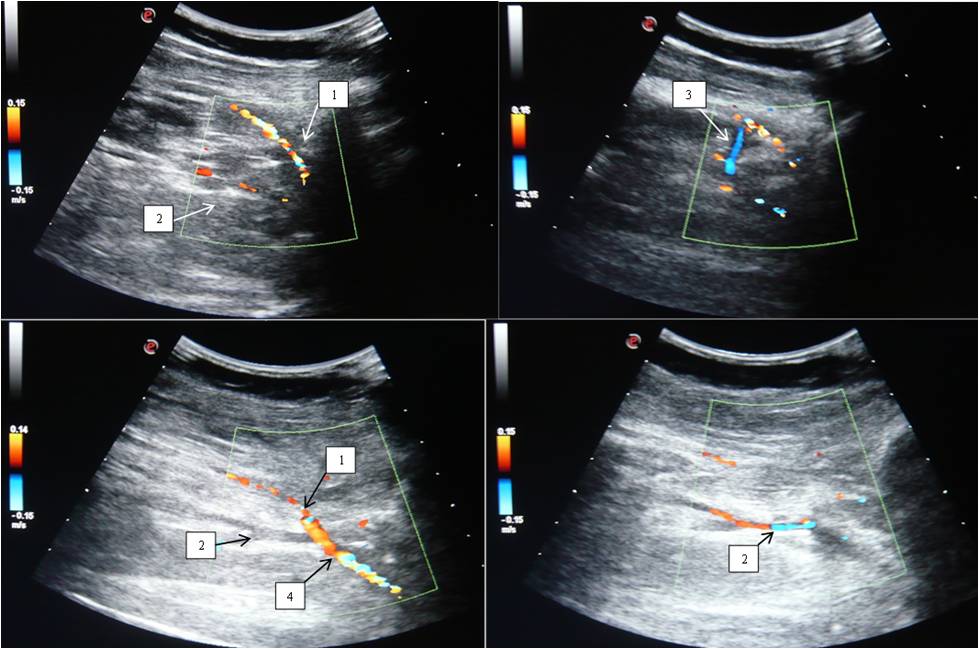

Two trunks of the PV in the distal part of the popliteal region were found in 85.7% of cases, and the vessel located medially from the PA was almost always larger than the one located laterally (Figure 5). Statistical analysis showed no statistically significant difference between the data of anatomical preparation and DS for this feature (p = 0.959).

Fig. 5. Duplex scan of the popliteal vein: (A, B, E) topography of the popliteal vein (level above the knee joint fissure); (C, D, F, G) two trunks of the popliteal vein below the knee joint cleft.

Notes: (1) Popliteal vein; (2) Popliteal artery.